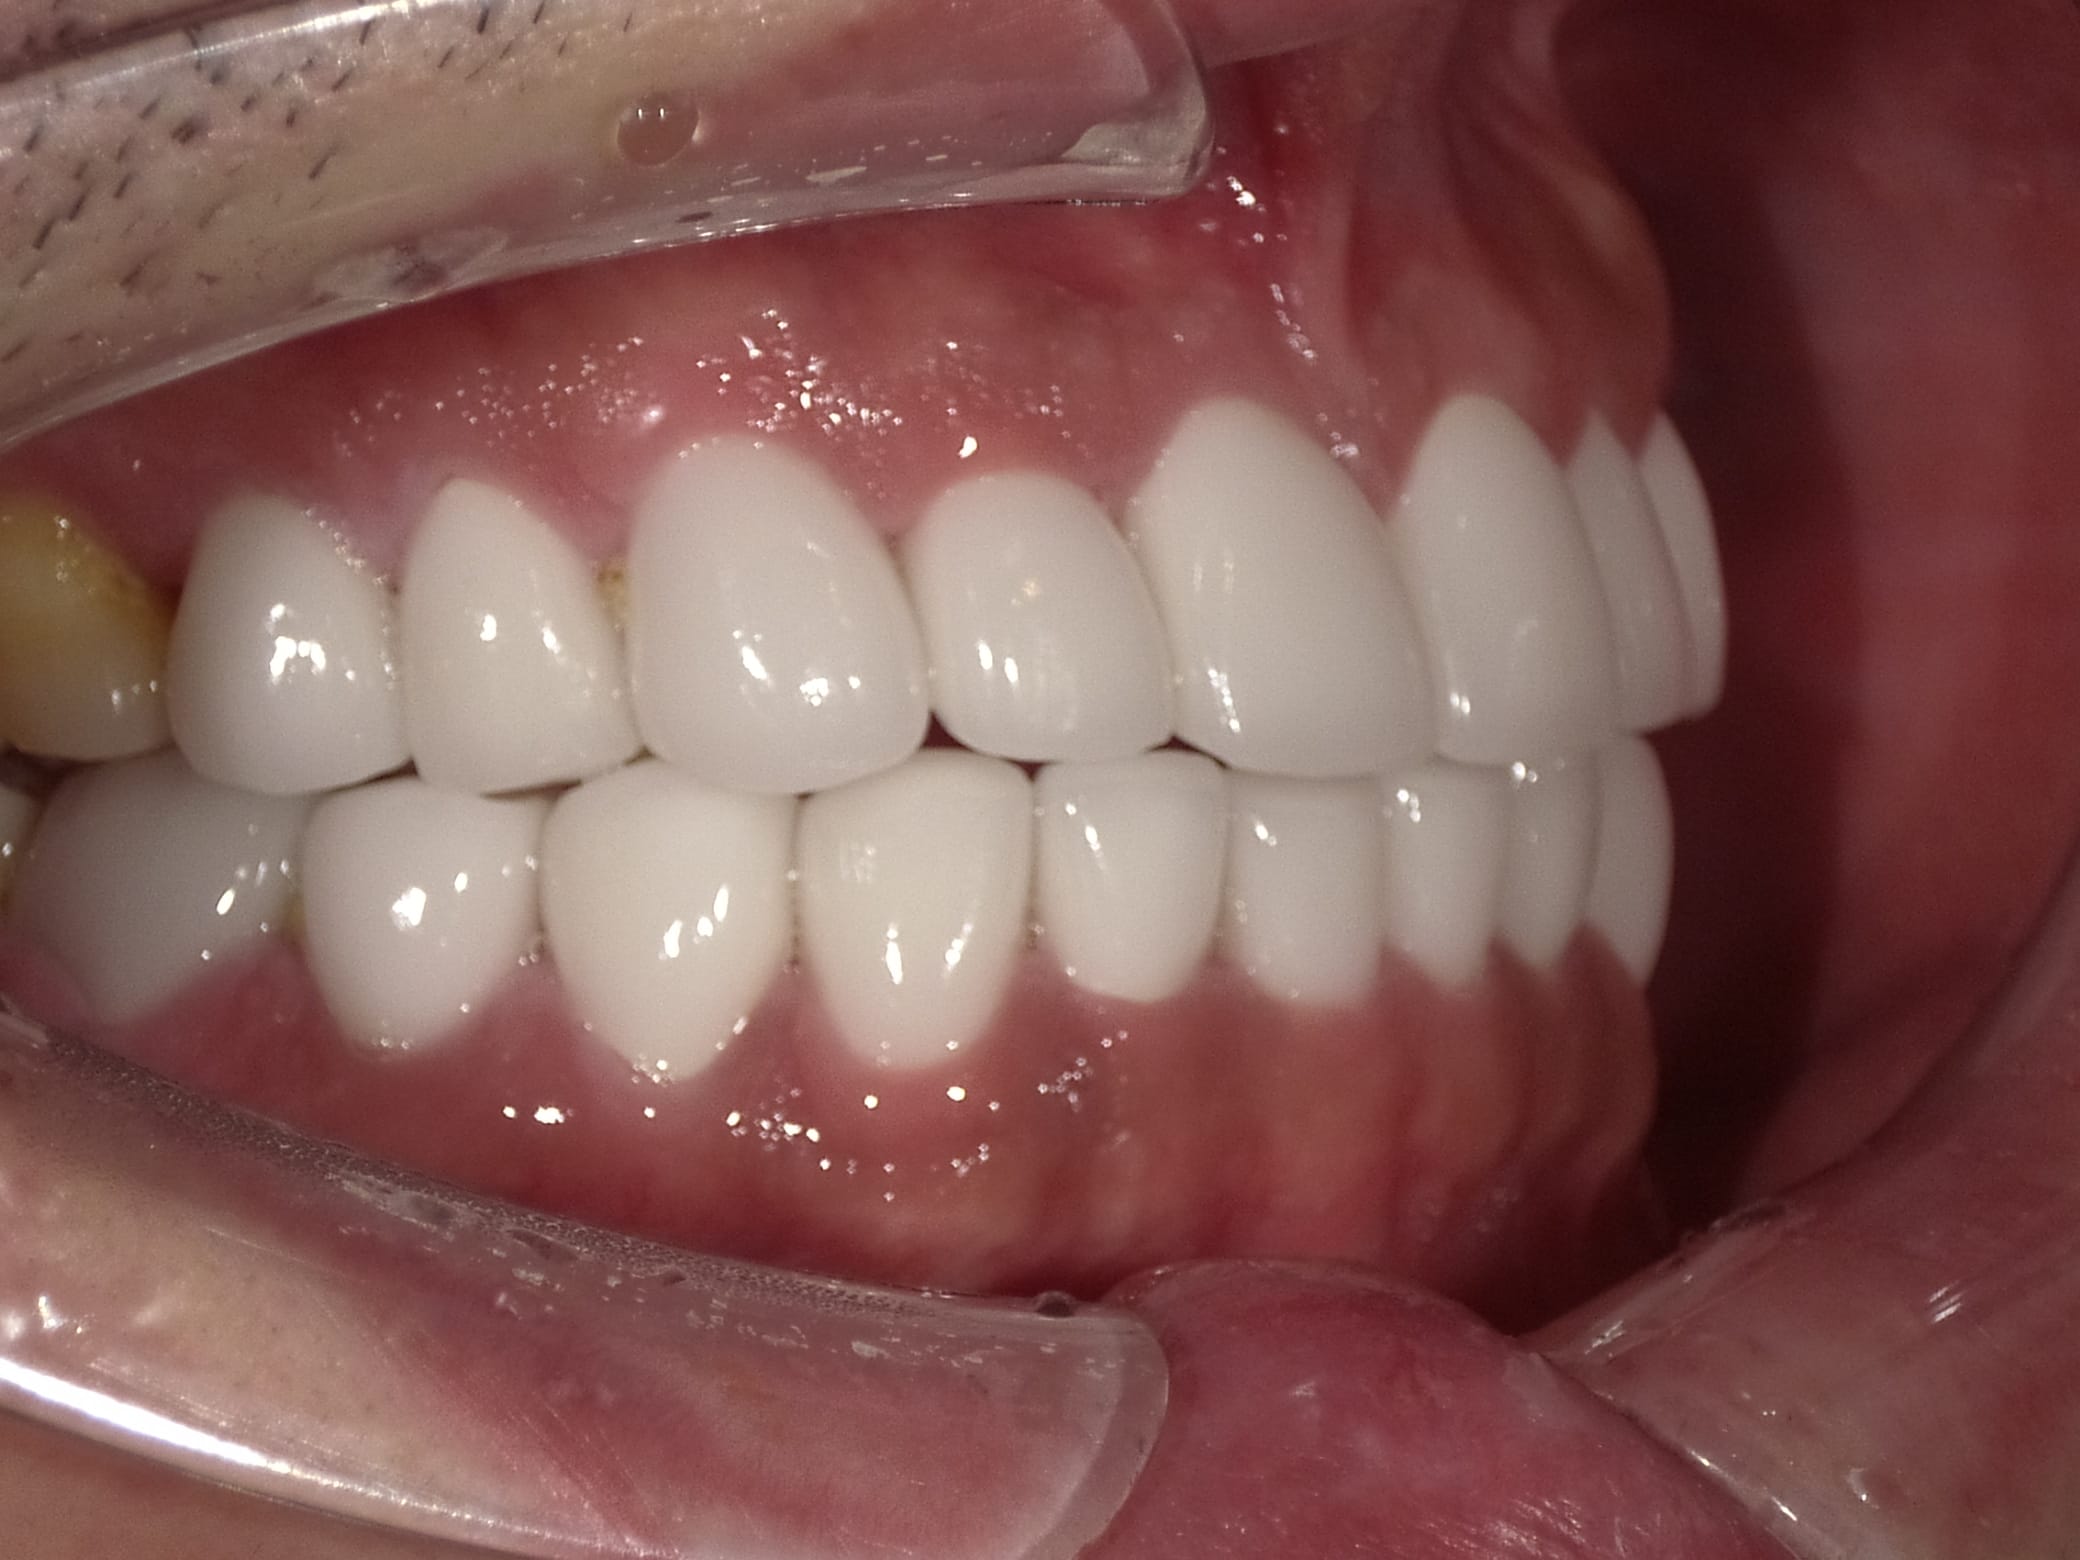

Case032

メジャーリーグでも活躍した元プロ野球選手の山口俊さんのセラミック治療を担当いたしました。

「他院で治療を受けたセラミックが欠けた」というのが主訴でしたが、よく診察するとセラミック欠けただけではなく、被せ物がしっかりと合っていないことが原因で歯茎の腫れがあり、歯石や汚れもつきやすい状態でした。また、歯列も若干歪んでいたので、この機会に全て治療いたしました。

治療後は透明感のある白さで、綺麗な歯並びになりました。また、セラミックをきちんと綺麗に削って適合よくセットしたことにより、歯茎の腫れも改善しました。

セラミックを入れた所の歯茎が腫れていて悩まれてる方はぜひご相談ください。

綺麗に削って適合よくセラミックをしてあげれば必ず改善します。